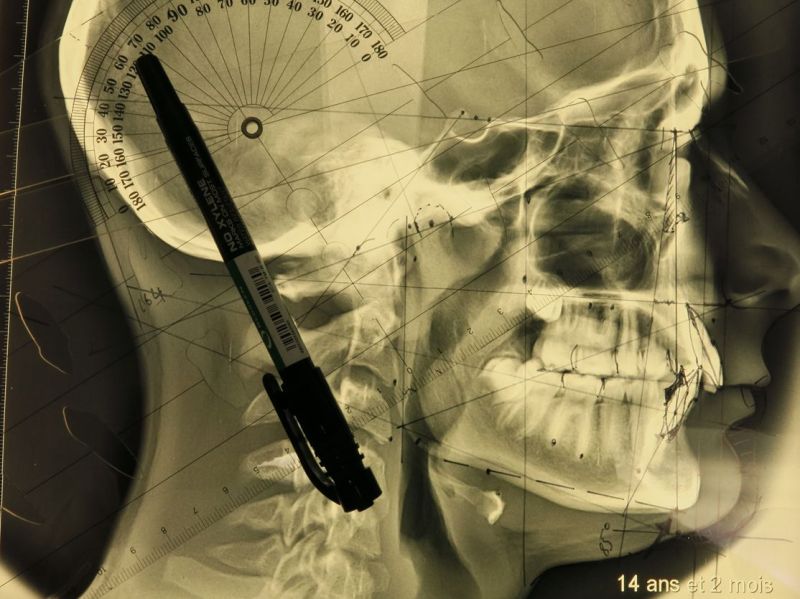

35-Céphalométrie 1: Comment comprendre le squelette au quotidien?

L'orthodontie c'est tout sauf les dents! Ah oui ? Je plaisante... Mais pas à 100%. Imaginez un spectacle de guignol (j'en avais tous les jeudis à la maternelle) Qu'y a-t-il…